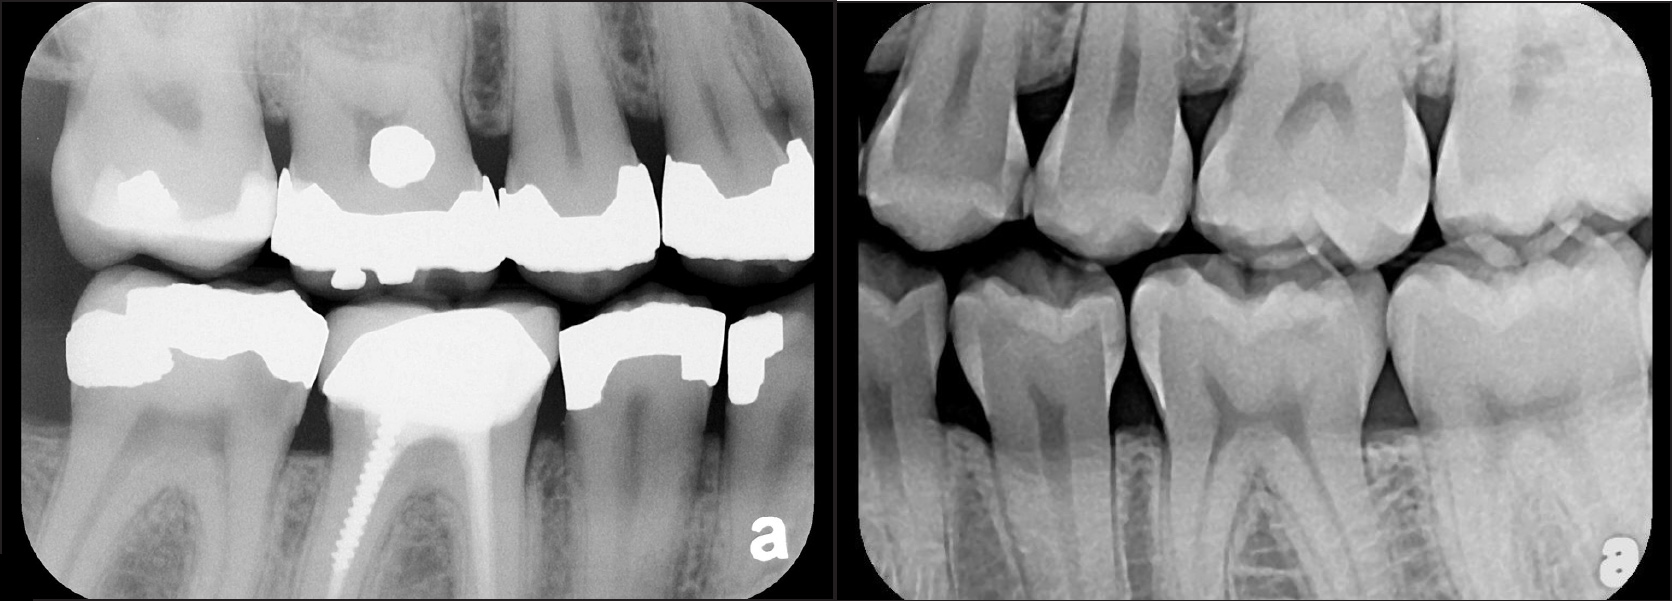

Fig 1. Left: Representative PSP BW radiograph with multiple restorative materials of varying radiographic densities. Tooth No. 31 demonstrates deep

caries on mesial aspect beneath the restorative. Radiolucency of carious lesion results from the low relative density of caries compared with healthy

tooth structure. Right: PSP BW radiograph optimized for view of multiple interproximal carious lesions.

Figure 1